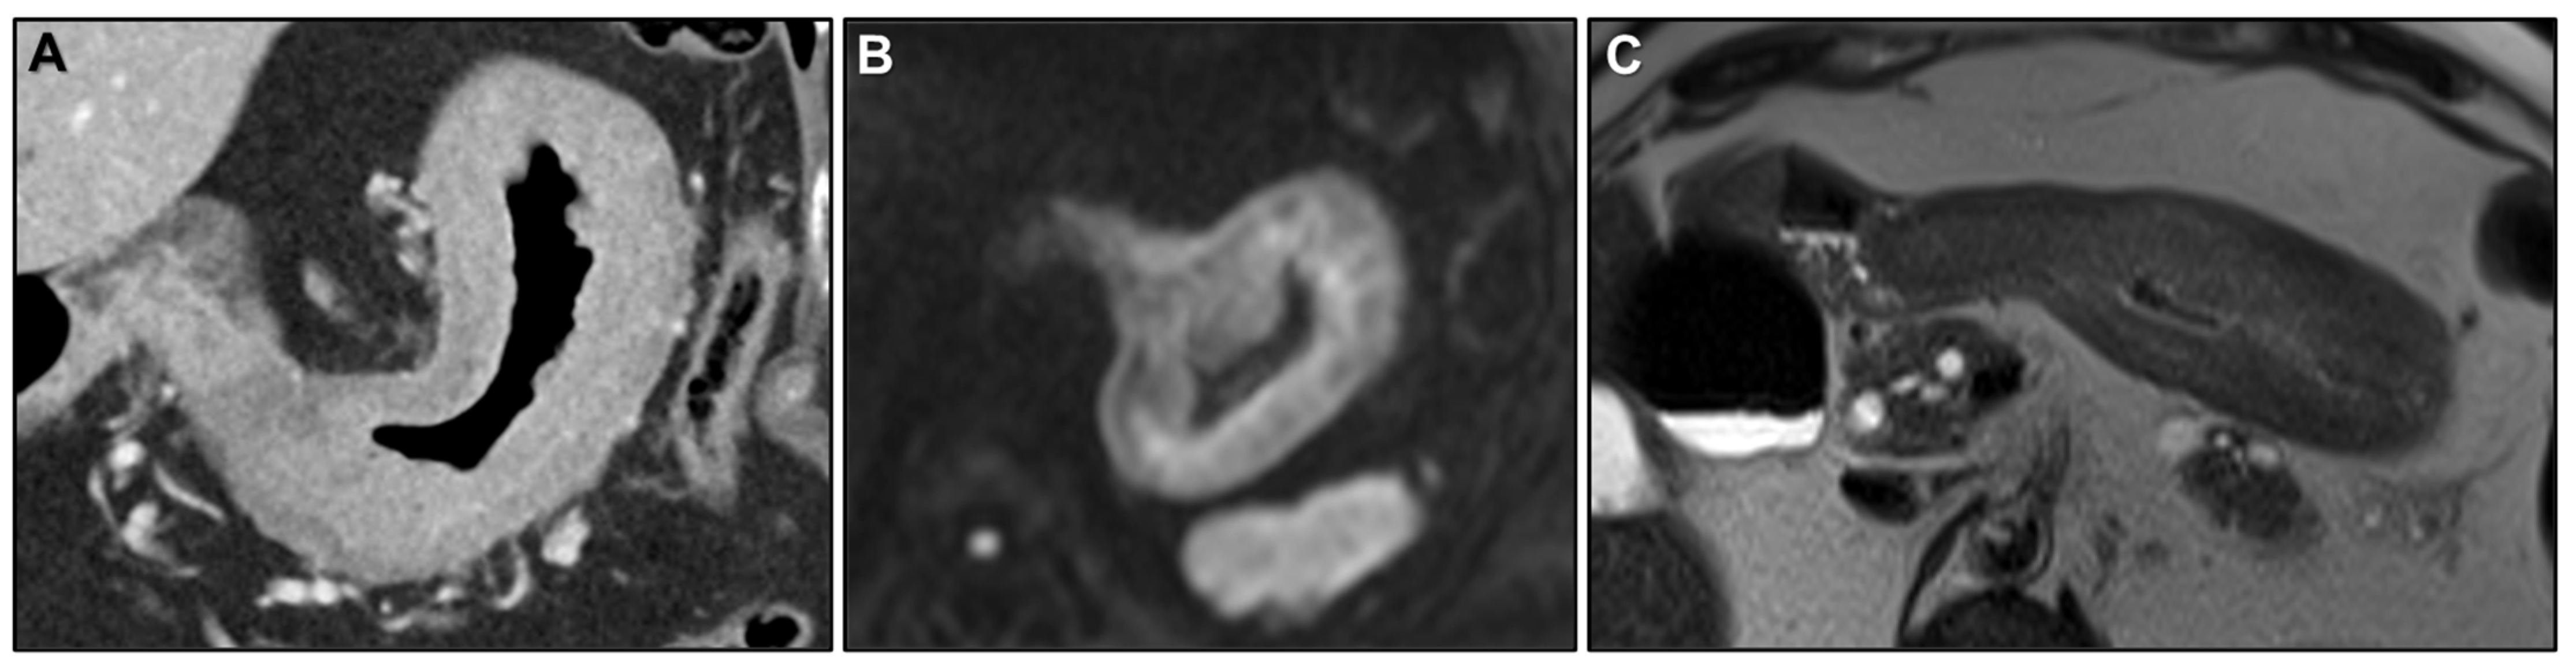

Malignant Target Sign